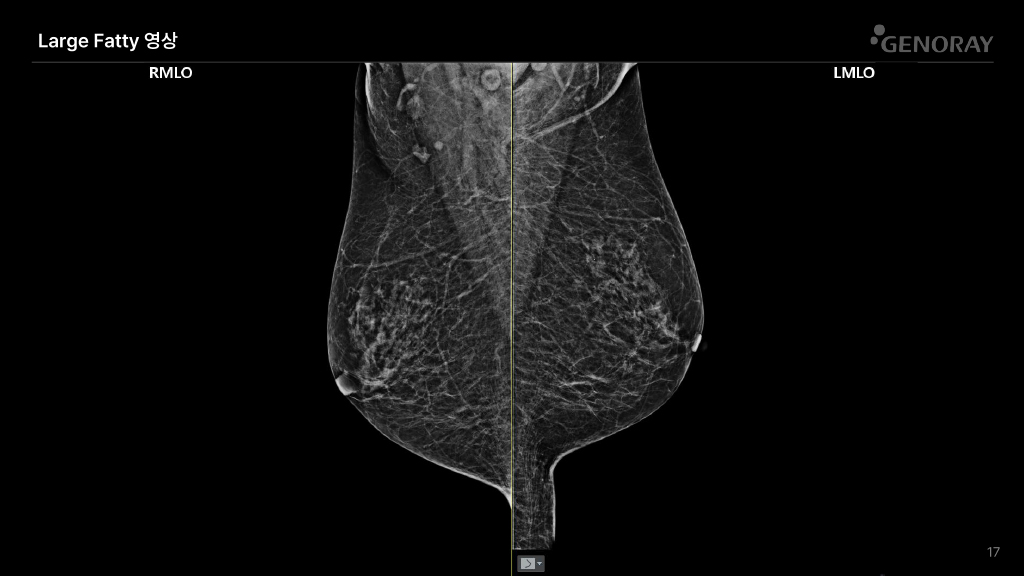

CLINICAL IMAGES

오랜 경험을 통해 축적된 노하우로 진단영상을 제공합니다.